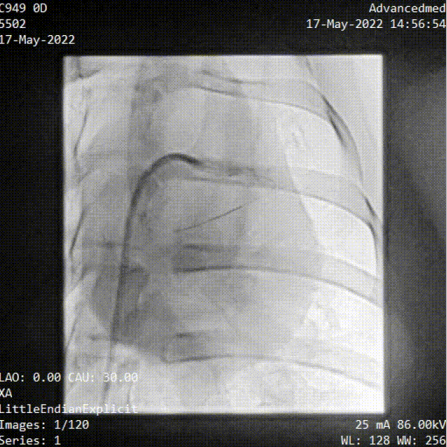

參與此次動(dòng)物實(shí)驗(yàn)的臨床主任醫(yī)師——中山大學(xué)附屬第七醫(yī)院特聘教授、復(fù)星醫(yī)療集團(tuán)心血管技術(shù)總監(jiān)彭宇程向億歐大健康介紹道,“本次動(dòng)物實(shí)驗(yàn)中,我們用機(jī)器人輔助完成了PCI、腎動(dòng)脈支架植入以及下肢血管覆膜支架(由深圳創(chuàng)心醫(yī)療提供)植入等3種常見血管介入手術(shù)類型,說明了這個(gè)平臺(tái)的兼容性還是挺好的,同時(shí)在手術(shù)中,導(dǎo)絲導(dǎo)管操作、球囊支架輸送都能夠順利實(shí)施?!?/p>

臨床上病人可能兼有多種疾病,醫(yī)生也有開展多種手術(shù)的要求,從意義來看,本次動(dòng)物實(shí)驗(yàn)既驗(yàn)證了睿心醫(yī)療血管介入手術(shù)機(jī)器人平臺(tái)的可兼容性,是全球首次在一臺(tái)設(shè)備、不更換傳送裝置的情況下同時(shí)完成了冠脈、腎主動(dòng)脈和外周三個(gè)部位的支架手術(shù),同時(shí)實(shí)驗(yàn)的成功也為其下一步進(jìn)入人體臨床試驗(yàn)提供安全、有效證據(jù)和參考依據(jù)。

(冠脈導(dǎo)絲遞進(jìn))